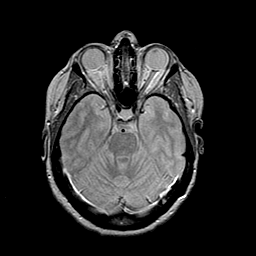

MR Study #2 -- Slice #19